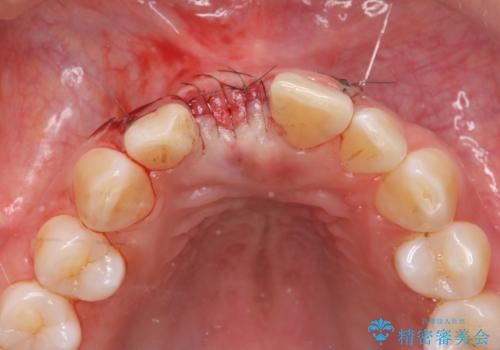

審美的・機能的に良好な位置に埋入するには、骨量が十分ではなかったため骨の造成を併用したインプラント埋入外科手術を行います。

前歯のインプラントを審美的に仕上げるには、インプラント周囲に十分な骨の量と厚みのある歯肉、そして埋入位置の精密な位置付けが重要です。